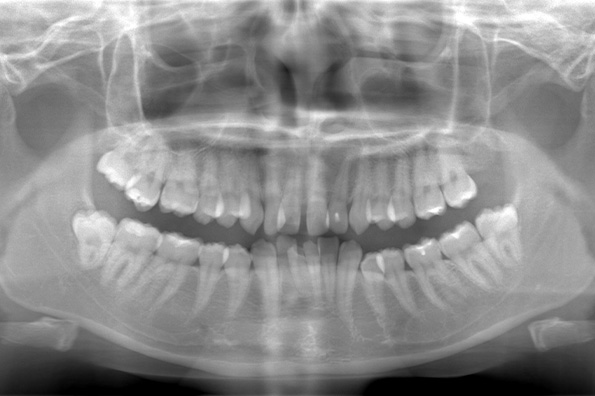

CASE 1

基本情報

| 年齢・性別 | 30代・女性 |

|---|---|

| 主訴 | 左右に分けて親知らずを抜きたい、できれば痛くなく抜きたい |

| 親知らずのはえ方 | 完全に出ていてまっすぐはえている |

| 抜歯期間 | 15分 |

| 抜歯費用 | 約2,000円(保険内) |

| 抜歯内容 |

何度か虫歯になり痛みはないが早めに抜きたい。 完全に頭が出ているため歯ぐきを切ったり骨を削らずに抜歯しました。 根の形も単純なため抜歯自体は5分もかからず上下ともに終わりました。 術後痛みや腫れも出ていません。 抜歯後は感染をしやすいため必ず抗生物質を飲み切ってください。 |